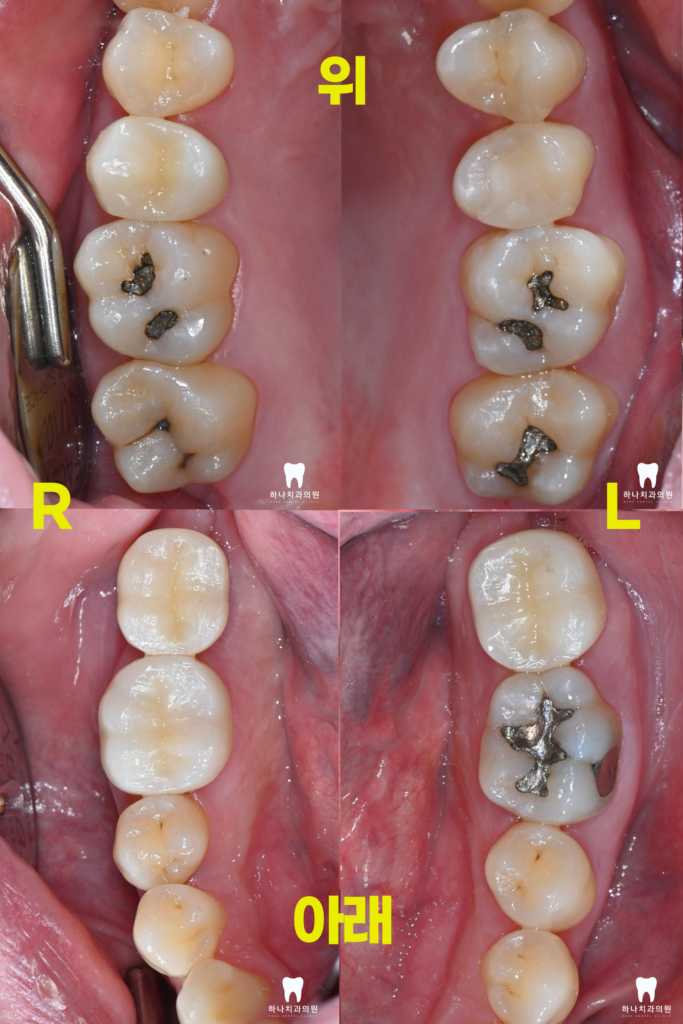

위 환자분께서는 30대 남성분으로

울산삼산동치과에 내원하셔서

진료받으신 경험이 있으신 배우자분의

추천으로 내원해 주셨는데요.

양쪽 어금니가 너무 아프고, 씹지도 못하신다며

치과가 무서워서 어렸을 때 말고는

와보신 경험이 없다고 말씀해 주셨습니다.

양쪽 아래 수평으로 매복되어 있는

사랑니가 관리되지 않아

바로 앞의 큰 어금니 뒤쪽으로

큰 우식을 공통적으로 가지고 있는

모습을 확인할 수 있었는데요.

오른쪽의 경우, 앞쪽에도 우식이

많이 진행된 상태였습니다.

따라서 양쪽에 매복되어 있는 사랑니를

발치하는데 심한 우식이 진행된 오른쪽의 경우

발치 후 임플란트, 왼쪽의 경우는 자연치 크라운을

진행하시기로 계획을 수립하였습니다.